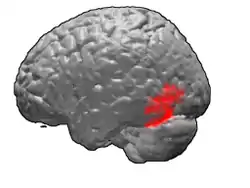

Brodmann area 37, or BA37, is part of the temporal cortex in the human brain. It contains the fusiform gyrus which in turn contains the fusiform face area, an area important for the recognition of faces.

This area is also known as occipitotemporal area 37 (H). It is a subdivision of the cytoarchitecturally defined temporal region of cerebral cortex. It is located primarily in the caudal portions of the fusiform gyrus and inferior temporal gyrus on the mediobasal and lateral surfaces at the caudal extreme of the temporal lobe. Cytoarchitecturally, it is bounded caudally by the peristriate Brodmann area 19, rostrally by the inferior temporal area 20 and middle temporal area 21, and dorsally on the lateral aspect of the hemisphere by the angular area 39 (H) (Brodmann-1909).[1]